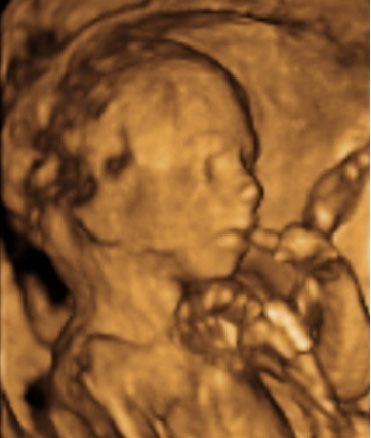

En la ecografía en 3D vemos a un bebé de 20 semanas de gestación se tapa la cara con ambos brazos y aprieta los puños. Se trata de un gesto innato que mantendrá en la cuna durante los primeros meses de vida.

Imagen de bebé tapándose la cara con ambos brazos

Ecografía Embarazo 2D y 3D - SEMANA 20

Lo primero aclarar que las ecografías en 3D no se realizan de rutina, mientras que las segundas siguen siendo las más extendidas. Una imagen en 3D se construye a partir de la información obtenida por sondas ecográficas especiales. Permite visualizar el rostro y el cuerpo del bebé con...